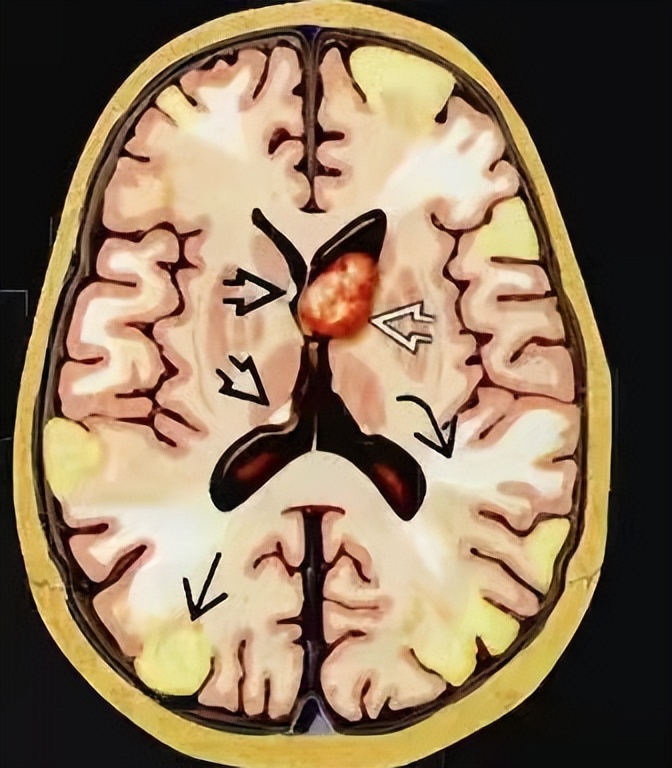

此时杨莹医生心中已经有了初步诊断,但需要影像检查进一步支持诊断,所以她给小王开了头部MRI检查,最终MRI结果显示小王双侧额、顶、颞、枕、岛叶皮层及皮层下多发异常信号,双侧室管膜下多发结节,考虑结节性硬化(见图2)。

图2

当杨莹医生看到MRI报告单,发现支持她最初的诊断,小王具有癫痫+脸上皮脂腺瘤+智力低下临床三联征,同时影像也符合,最后小王被诊断为结节性硬化。

图3

影像上皮质结节及室管膜下结节的发生率为95%(见图3),脑白质异常的发生率为40%-90%。临床治疗主要有mTOR*制剂抑**治疗,是对结节性硬化的病因治疗。抗癫痫药物治疗缓解抽搐。部分可以生酮饮食,可以减少癫痫发作。